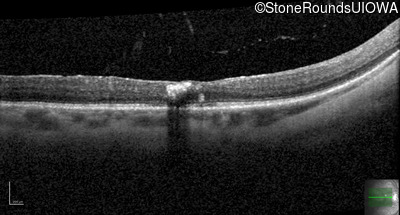

Age at visit: 47 years

OD OS

This 47 year old woman began wearing glasses at age 5 and had cataract surgery at age 32. At that time her doctor noticed a retinal abnormality.

Age at visit: 49 years

Age at visit: 50 years

Age at visit: 51 years